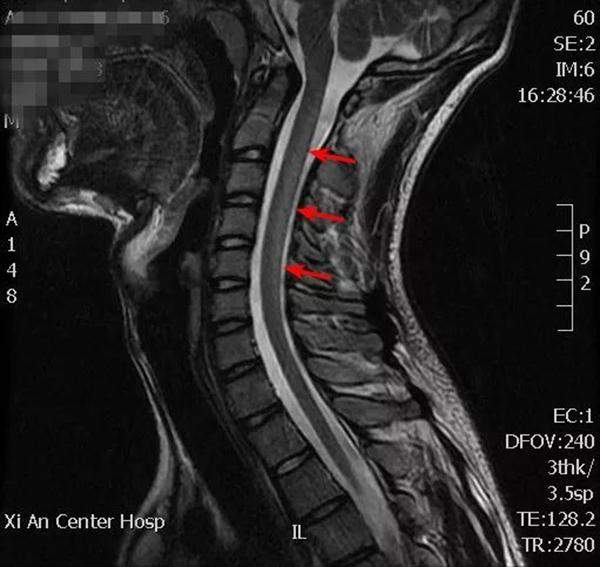

《中國消費者報》瞭解到,兩位患者均為在校大學生。按照醫院的説法,一名18歲的大學生,在入院前2周出現了四肢遠端對稱性麻木、乏力等症狀。入院後經過詳細的體格檢查,患者的主要神經系統損害被鎖定在脊髓和周圍神經系統,經後續的肌電圖檢查及實驗室化驗,神經科醫師懷疑患者為維生素B12缺乏導致的脊髓病變,即亞急性聯合變性。在進一步的頸椎磁共振檢查後更加證實了診斷。